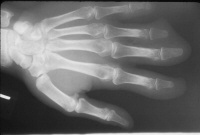

Initial injury:

Image Image Image